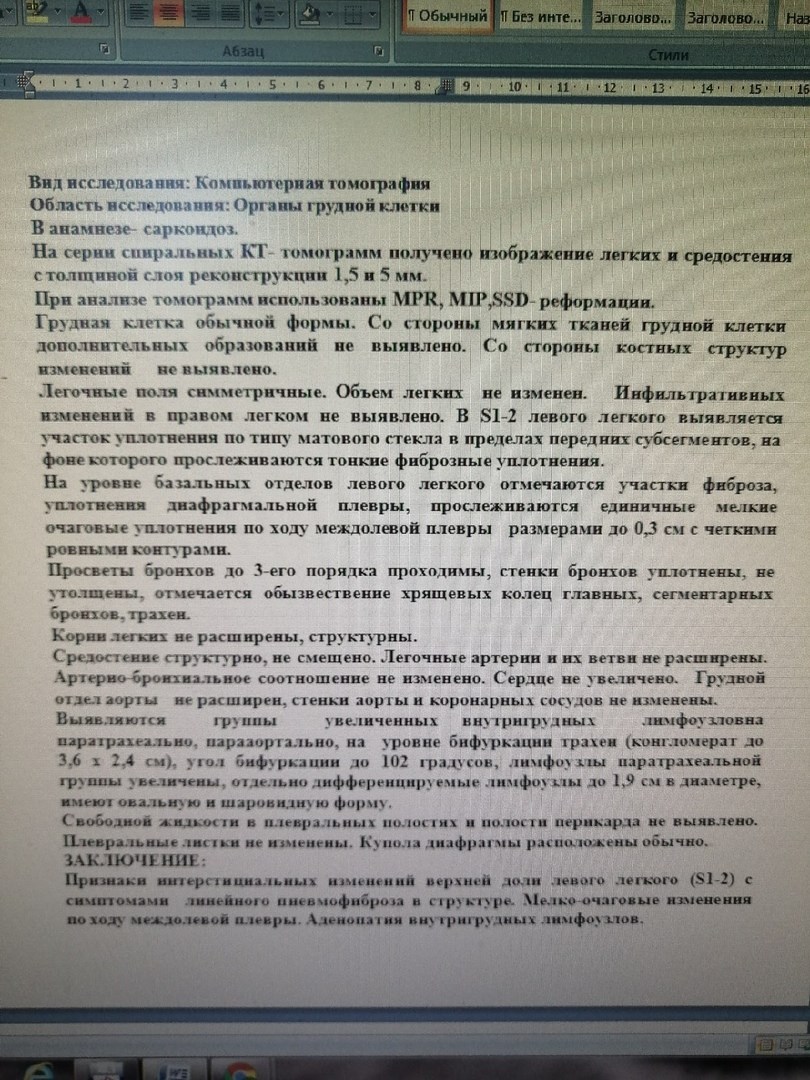

Диагностика лимфомы Ходжкина с помощью ПЭТ и КТ

Раздел: Светлые идеи